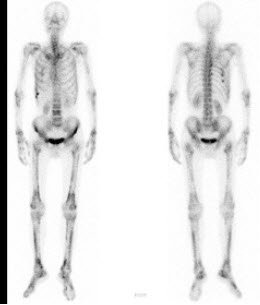

275、多项选择题

男,68岁,肺癌术后半年,诉双下肢疼痛3个月,行全身骨显像如图,可能的诊断是()

A.双侧下肢骨骨转移瘤

B.热髌征存在

C.广泛骨转移瘤

D.双下肢肥大性骨关节病

E.以上都不是